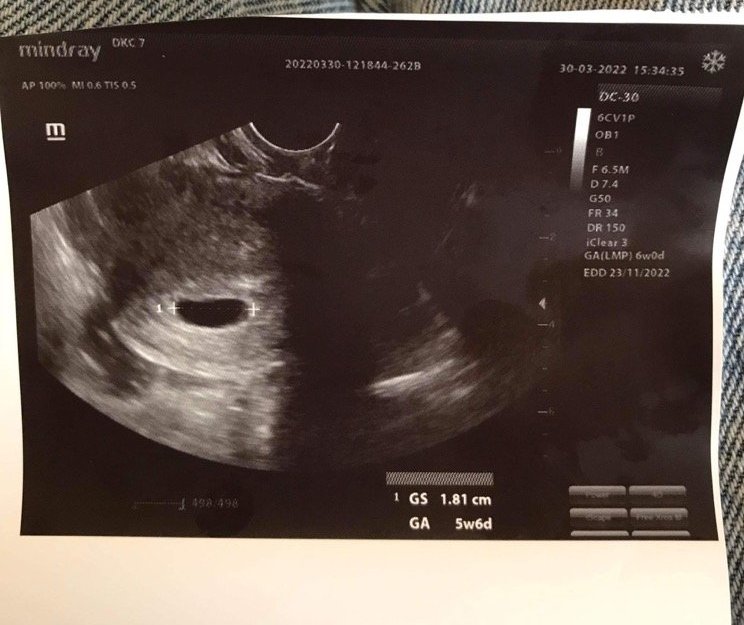

Понеже беше очаквано установих бременноста с ранен тест за бременност 3 дни преди закъснението.Два дни преди датата на М имах 2-3 капки кръв и отидох на доктор.Изписаха ми утрогестан , който вчера го спрях.Вече съм 8 седмица и чухме пулс.Първа бременност ми е а датата на термина ми е 07.11.2022!Лека бременност на всички!